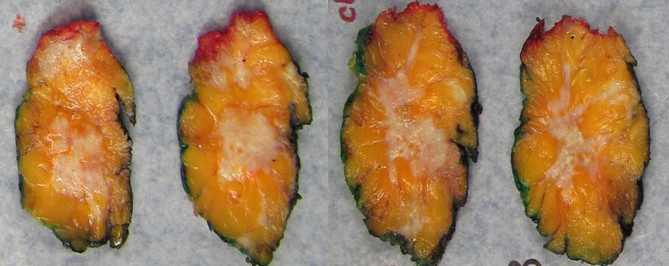

Gross description

- Gross appearance of tumor may indicate degree of pathological response

- Tumors with poor response demonstrate a firm, gritty and spiculated appearance (i.e., no difference from typical untreated tumors)

- Response can be indicated by fibrosis or softening of the tumor bed (Mod Pathol 2015;28:1185)

- Tumors with partial response can be nodular, multifocal with and less well defined borders (Breast 2022;62:S25)

- In cases of complete response, the tumor bed may be soft and indistinguishable from normal breast tissue

- Tumor mapping with radiographs, photographs or drawings of the sectioned gross specimen is recommended (Mod Pathol 2015;28:1185)

Gross images